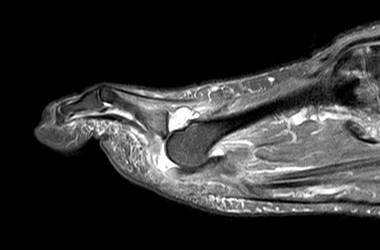

Die Überbelastung des Metatarsale II und III im distalen Bereich äußert sich in Druckschmerzen und Schwielenbildung plantar unter den Metatarsale II und III Köpfen (Abb. 1). Auch degenerative Veränderungen der plantaren Kapsel und der plantaren Platte der Metatarsophalangealgelenke treten auf, was zu einer Insuffizienz der Grundgelenke mit Subluxation oder Luxation der Kleinzehen führt (Abb. 2 und 3).

Zum Lesen der Bildbeschreibung und zur Vollansicht bitte die Bilder anklicken. Bilder: C. Hase